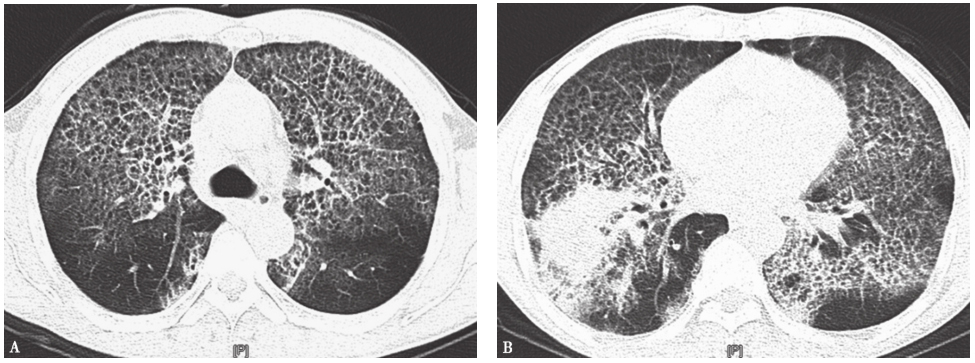

胸部CT:双肺可见弥漫性网格状密度增高影,支气管壁增厚;右下肺可见团片状密度增高影,边缘不清,密度不均,有小空洞形成;双侧胸膜肥厚粘连,气管、支气管通畅,纵隔淋巴结增大(图1)。

图1入院第2天胸部CT表现

胸部CT可见双肺弥漫性网格状密度增高影(A),右下肺团片状密度增高影(B)